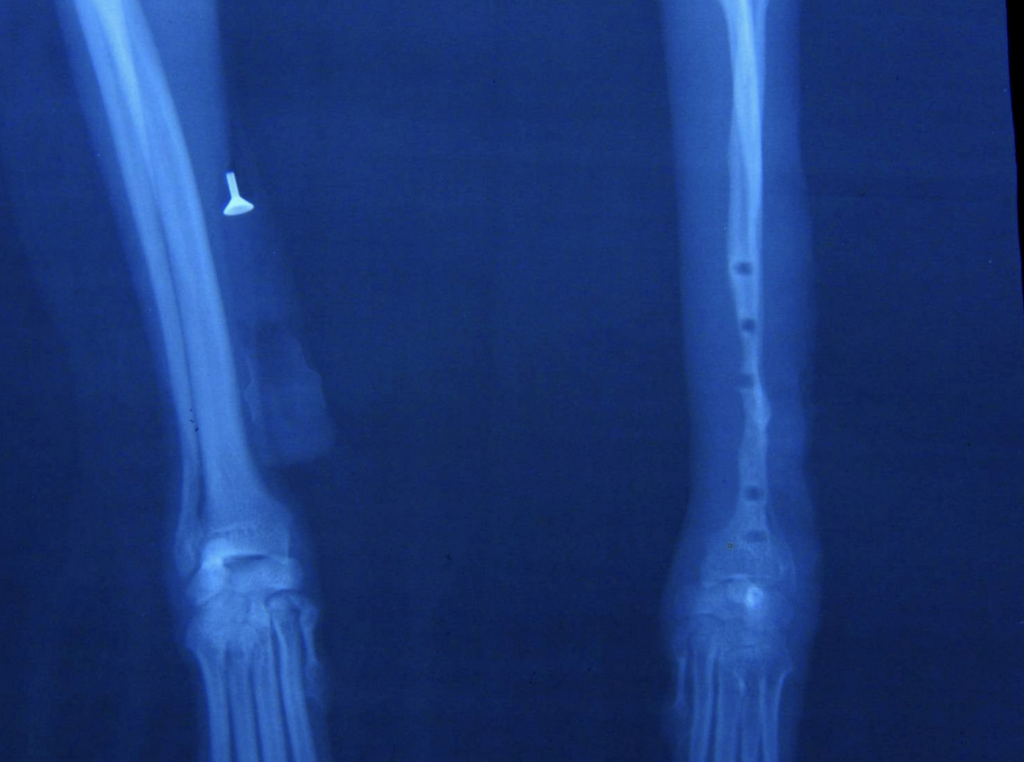

「骨折ですね。手術をして金属プレートで固定しましょう。」

上手くいく訳のない手術をして骨折が治らなければ

その犬の治癒力のせいにされたり・・

【目からウロコの骨折の予防と治療】

・小型犬はなぜ骨折する?

・従来の骨折治療法

・新しい骨折治療法

・骨再生法